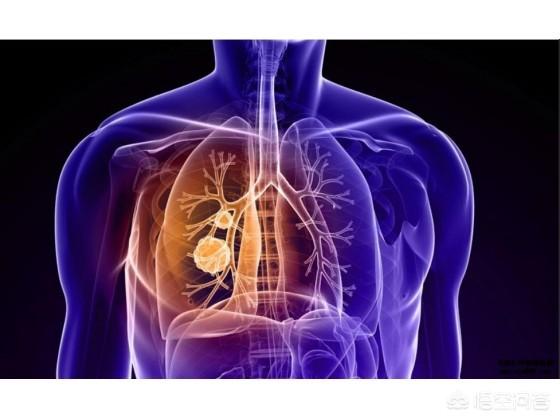

Ce sujet est plutôt lourd, mais c'est une situation à laquelle de nombreux patients atteints de cancer du poumon et leurs familles doivent faire face. Les taux d'incidence et de mortalité du cancer du poumon sont les plus élevés de toutes les tumeurs malignes. Bien que les méthodes de traitement du cancer du poumon soient relativement plus nombreuses, l'effet global n'est pas optimiste. Lorsque tous les traitements sont inefficaces et que l'état physique du patient se détériore progressivement, diverses situations mettant sa vie en danger se produisent. Il n'y a pas que le cancer du poumon, en fait, tous les patients atteints de cancer finissent par mourir non pas du cancer lui-même, mais de la défaillance de plusieurs organes.

Le décès des patients atteints d'un cancer du poumon peut être dû aux causes suivantes

1) L'insuffisance respiratoire, communément appelée manque d'air du patient, est la plus fréquente chez les patients atteints d'un cancer du poumon avancé. Le cancer central du poumon obstrue la trachée et les bronches principales, ce qui rend difficile l'entrée de l'air, et en cas d'atélectasie pulmonaire importante, le patient souffrira progressivement d'essoufflement et de dyspnée. Certains patients développent un épanchement pleural important dû à des métastases pleurales, qui comprime les tissus pulmonaires et empêche la réouverture des poumons. Chez d'autres patients, les lésions pulmonaires sont trop nombreuses et la surface effective de la membrane respiratoire est considérablement réduite. Toutes ces raisons finissent par entraîner une oppression thoracique, un essoufflement, une respiration assise et, finalement, une insuffisance respiratoire.

2. infection grave L'infection pulmonaire est une comorbidité très fréquente et une cause de décès chez les patients atteints de cancer du poumon. En raison de la présence de lésions pulmonaires et de l'obstruction des voies respiratoires, les expectorations et les bactéries sont difficiles à évacuer chez les patients atteints d'un cancer du poumon à un stade avancé, et toutes sortes d'infections bactériennes et fongiques peuvent facilement se produire. En raison de la fonction immunitaire extrêmement faible, il est difficile de contrôler les infections pulmonaires même avec l'utilisation d'antibiotiques de pointe, et les patients souffriront d'une septicémie et d'un choc infectieux, ce qui mettra leur vie en péril.

3. émaciation extrême : la tumeur elle-même est une sorte de maladie qui épuise les nutriments et l'énergie de l'organisme. Les patients atteints d'un cancer du poumon avancé souffriront également d'une perte d'appétit, de nausées et de vomissements, d'un apport insuffisant de nutriments et de la consommation constante de cellules tumorales, de sorte que les patients ont tendance à souffrir de ce que la médecine appelle une "stase liquidienne maligne", avec un manque d'apport de nutriments à l'ensemble de l'organisme et, en fait, à mourir d'une défaillance de plusieurs organes. Le patient finit par mourir d'une défaillance de plusieurs organes.

4) Hémoptysie et asphyxie De nombreux patients atteints de cancer du poumon présentent le symptôme du sang dans les expectorations, en particulier dans le cas du cancer central du poumon, lorsque la tumeur envahit les grands vaisseaux sanguins, une hémoptysie peut se produire, et le sang s'écoule dans les voies respiratoires, provoquant une asphyxie et mettant la vie du patient en danger.

5. coma convulsif Lorsque la lésion des métastases cérébrales du cancer du poumon s'aggrave progressivement, un œdème cérébral, une augmentation de la pression intracrânienne ou même une hernie cérébrale apparaissent, le patient souffre de maux de tête intenses et de vomissements, et la lésion métastatique dans les parties importantes déclenche une épilepsie secondaire, le patient convulse et tombe dans le coma, ce qui met sa vie en danger.

6. troubles électrolytiques 30 % des patients atteints de cancer du poumon présentent un syndrome cancéreux associé, une sécrétion d'hormones ectopiques et des troubles électrolytiques tenaces, tels qu'un faible taux de sodium et de potassium, et des troubles électrolytiques graves qui interfèrent avec la conduction électrique cardiaque et mettent la vie en danger.

7) Thrombose : le sang des patients atteints d'un cancer du poumon avancé est en état de coagulation élevée, ce qui favorise la thrombose. Lorsque le thrombus ou l'embole cancéreux est délogé vers des organes importants, il provoque un infarctus du myocarde, un infarctus cérébral, une embolie pulmonaire, etc. et cliniquement, nous avons rencontré des cas de décès par infarctus du myocarde chez des patients ayant subi une chimiothérapie soudaine.

8. les foyers métastatiques provoquent une défaillance des organes Le cancer du poumon peut métastaser dans le foie, la cavité abdominale et les reins. Lorsque les foyers métastatiques sont trop nombreux et trop grands, ils ne produisent pas seulement des symptômes de compression et d'obstruction, mais affectent également les fonctions hépatiques et rénales, entraînant une insuffisance hépatique et une insuffisance rénale, et des métastases étendues dans la cavité abdominale provoqueront une obstruction intestinale, de sorte que le patient ne pourra pas s'alimenter et mourra d'épuisement.

9. décès liés au traitement Les décès liés au traitement du cancer du poumon ne sont pas rares. Les méthodes de traitement du cancer du poumon, telles que la chimiothérapie, la radiothérapie, la thérapie ciblée et l'immunothérapie, ont toutes des effets secondaires toxiques correspondants, et un très petit nombre de patients sont décédés parce qu'ils n'ont pas pu tolérer les diverses toxicités au cours du traitement.